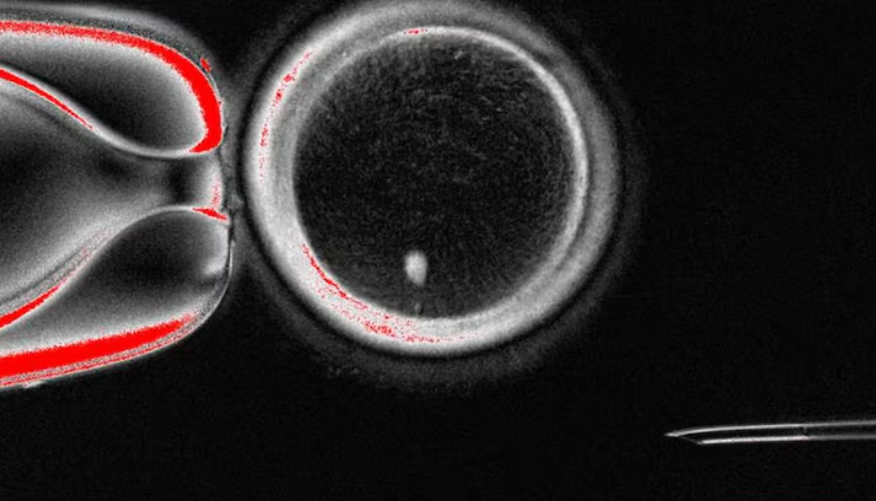

Alimlər ilk dəfə olaraq insan dərisi hüceyrələrindən yumurta hüceyrələri hazırlamağı bacarıblar.

AzEdu.az-ın xarici mediadan əldə etdiyi məlumata görə, Oregon Health & Science Universitetinin tədqiqatçıları tərəfindən aparılan araşdırma nəticəsində adi dəri hüceyrələri “induksiya olunmuş pluripotent kök hüceyrələr”ə çevrilib və onlardan yumurta hüceyrəsi formalaşdırılıb.

Mütəxəssislərin sözlərinə görə, bu nailiyyət xüsusilə təbii yolla yumurta əldə edə bilməyən qadınlar üçün gələcəkdə yeni ümidlər yarada bilər. Lakin hazırda laboratoriyada yaradılan yumurtalarda çoxlu xromosom xətaları müşahidə olunur və onların real istifadəsi üçün uzunmüddətli sınaqlara ehtiyac var.

Alimlər hesab edirlər ki, bu texnologiya gələcəkdə qısırlığın müalicəsi və genetik xəstəliklərin öyrənilməsi sahəsində yeni imkanlar aça bilər.